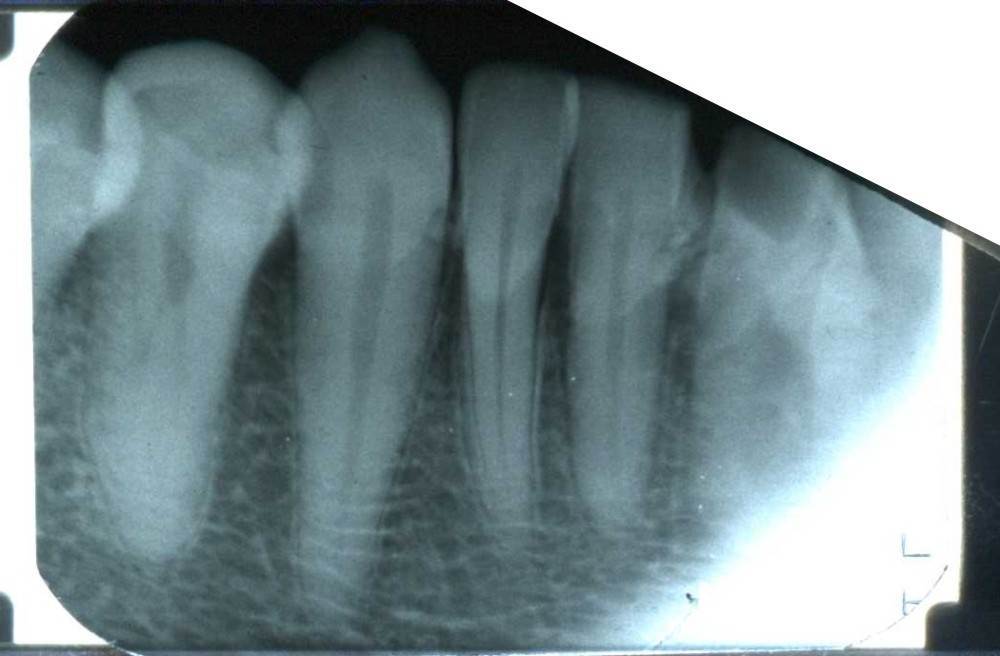

Sergey-010101 Опубликовано 5 октября, 2025 Поделиться Опубликовано 5 октября, 2025 (изменено) Здравствуйте. У меня на нескольких передних зубах большие камни, рецессия десны, на миллиметров 5-6 камень опускается спереди и сзади зуба. В одной стоматологии предложили чистку ручными инструментами. В другой аппаратом Вектор. Что являет более безопасным для чистки камней на корнях? Какой вариант выбрать? Вектор вроде ультразвук использует. А пишут что ультразвуком камни на корнях вредно чистить. Есть ли у Вектора какие то варианты? Насадки? Если выбрать этот способ есть моменты которые нужно уточнить? Обратить более подробное внимание. Изменено 5 октября, 2025 пользователем Sergey-010101 Ссылка на комментарий

Sergey-010101 Опубликовано 5 октября, 2025 Автор Поделиться Опубликовано 5 октября, 2025 И что делать если будут шататься потом, чтобы сохранить? Как нарастить десну кость? Немного есть мнения что есть риск потери. Но в целом несколько врачей сказали что могут даже не шататься. Убыль кости есть на 2-3 мм в некоторых местах, но корень более чем на половину в кости. Ссылка на комментарий